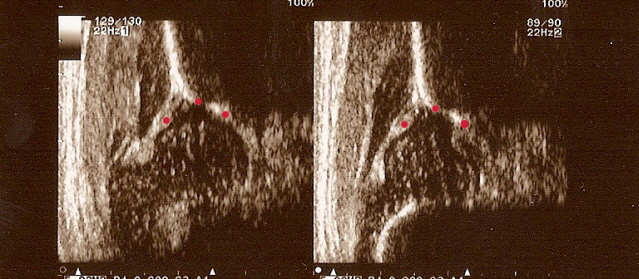

2.Otrzymanie następującego obrazu usg(rys.l):

- 1 sylwetka kości biodrowej z występem kostnym na końcu

- 2 wyraźny,umożliwiający identyfikację obrąbek stawowy

- 3 gałąź dolną kości biodrowej jako jasne,dobrze zaznaczone,silne echo

rys.nr.2

- 2 gałąź dolną kości biodrowej jako jasne,dobrze zaznaczone,silne echo

- 3 wyraźny,umożliwiający identyfikację obrąbek stawowy

przekrojowy obraz usg w standardowej płaszczyźnie Brak któregokolwiek ze składników uniemożliwia prawidłową ocenę

i należy badanie powtórzyć.W taki sposób otrzymany obraz pozwala na wykreślenie kątów za pomocą następujących linii(rys.2):